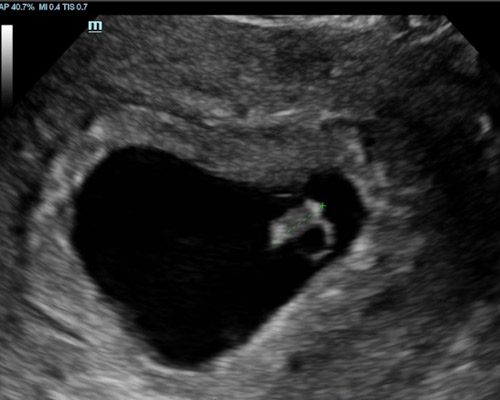

Our Scans

During a reassurance scan, you may see your baby’s heartbeat, movements, position, and general activity on the ultrasound screen.